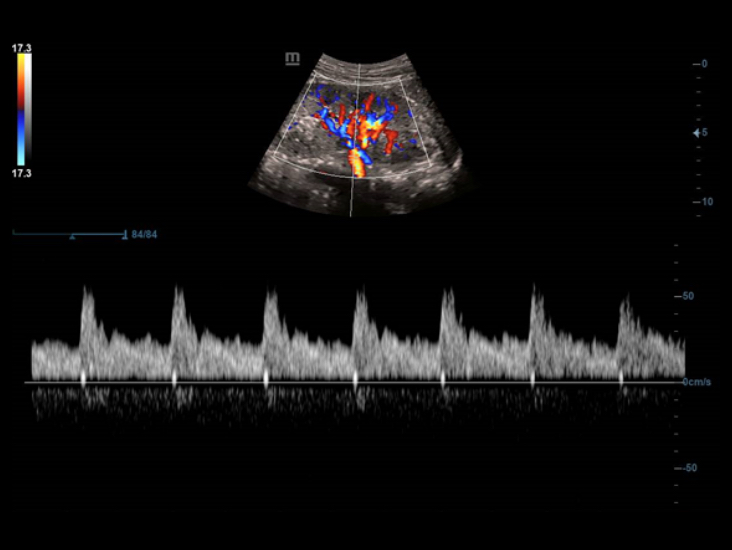

DC-40 con Full HD offre una gamma di strumenti in grado di massimizzare l'accuratezza diagnostica con praticitĂ . DC-40 con Full HD puĂČ essere utilizzato in diagnostica per immagini generale, ginecologia/ostetricia e cardiologia e costituisce una soluzione completa per le applicazioni cliniche tradizionali, con un flusso di lavoro semplificato per il massimo dell'efficienza.

Smart Track

Con un semplice tocco, Smart Track consente di ottenere una visualizzazione ottimizzata rapida e intelligente dell'imaging vascolare. ? in grado di ottimizzare lo spettro del colore, del power e del PW mediante il funzione di tracking automatico e ridurre i passaggi che richiedono molto tempo, semplificando cosĂŹ il flusso di lavoro per gli esami vascolari.